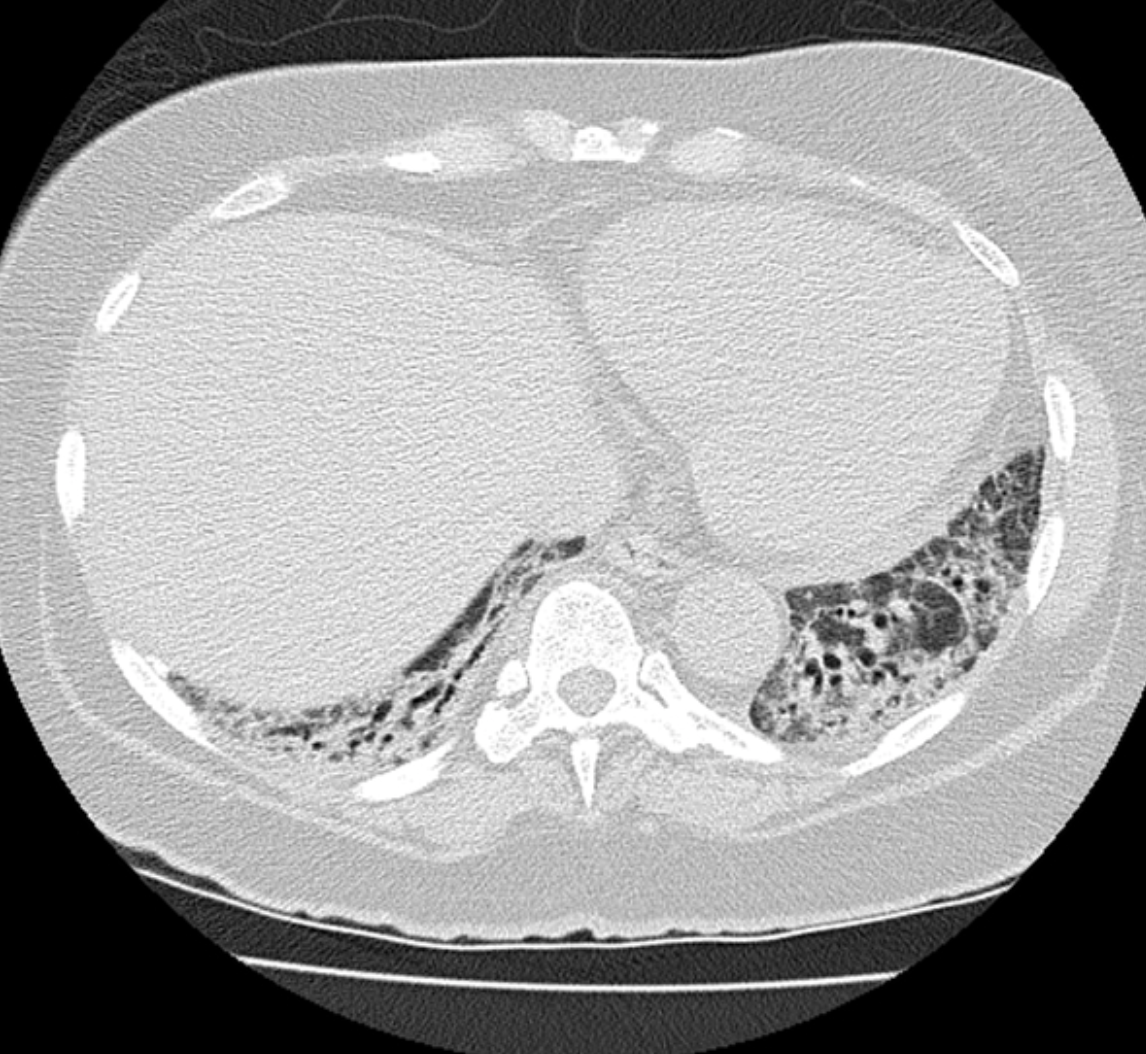

ACUTE INTERSTITAL PNEUMONIA

• Appears similar to ARDS but often with a symmetric Lower Lobe distribution

• EXUDATIVE PHASE (shown in pic one case)

• GGO

• Consolidation

• ORGANISING PHASE (pic two)

• architectural distortion

• traction bronchiectasis

• Honey combing